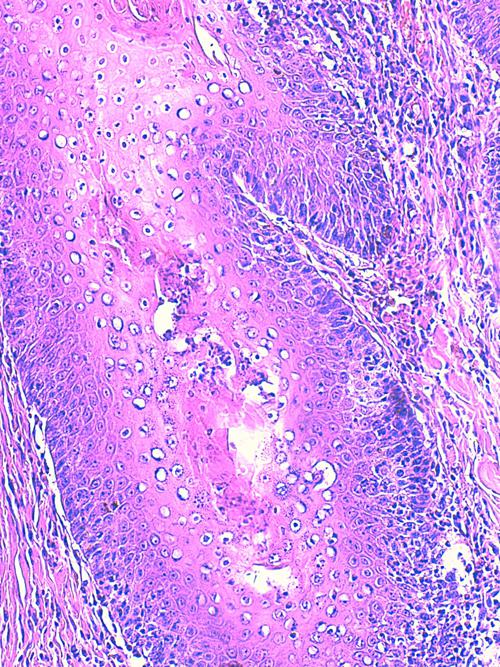

Photo 18 (Hémalun Eosine X 200) peau velue : Certains éléments vermiformes sont

inclus dans de petites logettes au sein de la paroi des follicules pileux,

ici un même élément vermiforme en coupe transversale et longitudinale.

Légendes de la Photo 18 :

- Étoile rouge : lumière du follicule pileux

- Double flèche verte : GEE

- Double flèche bleue : derme inflammatoire péri-folliculaire (infiltrat riche en granulocytes éosinophiles et en palsmocytes)

- Flèches jaunes : élément vermiforme rond cylindrique non segmenté

Photo 19 (Hémalun Eosine X 400) peau velue : Vue rapprochée de la Photo 18.

Ici un même élément vermiforme en coupe transversale et longitudinale :

élément rond cylindrique non segmenté à cuticule lisse et fine.

Il semble y avoir des cellules musculaires et une cavité centrale contenant des organes.

Légendes de la Photo 19 :

- Étoile verte : “matériel organique” dans la cavité centrale

- Flèches turquoises : cellules musculaires sous-cuticulaires

- Flèches jaunes : cuticule du ver